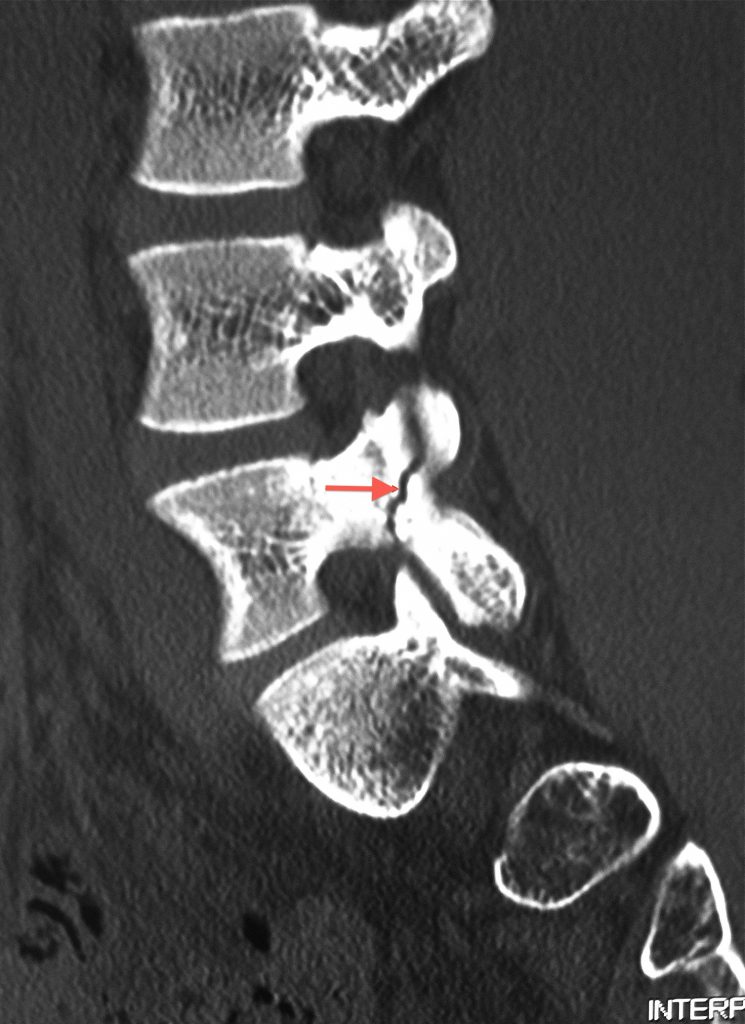

Espondilólise.